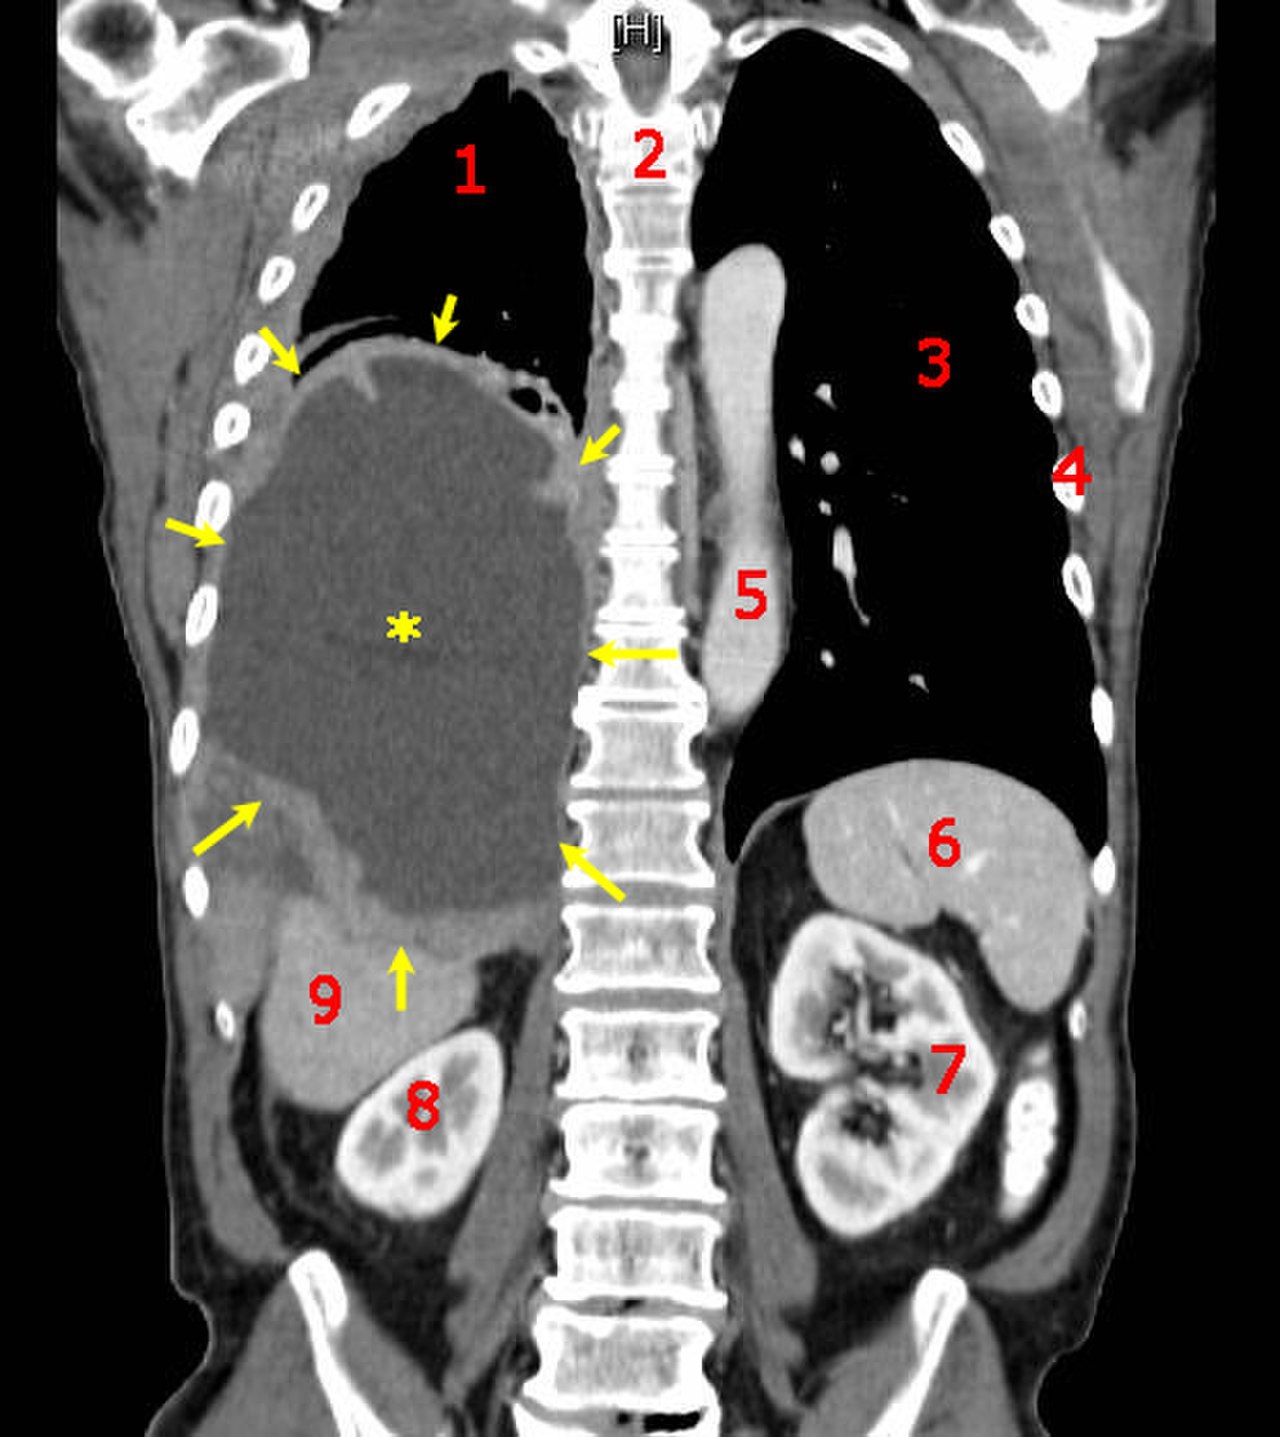

X Ray Multiple Part Of Child S Body Multiple Disease Stroke Brain Tumor Rheumatoid Arthritis Sinusitis Gouty Arthritis Etc Skull Chest Lung Heart Spine Arm Hand